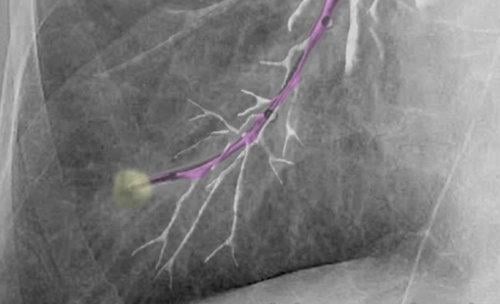

"Body Vision provides a great tool that has changed the way we approached peripheral nodules. Its unique technology creates augmented reality with the ability to see fluoroscopically invisible lesions and the pathways under the live fluoro, while tracking a patient breathing," said D. Kyle Hogarth, M.D., FCCP, president of the Society for Advanced Bronchoscopy, associate professor of medicine, director of bronchoscopy at the University of Chicago. "Once the technology has guided us to the lesion, we confirm the lesion's relationship to the airway with radial-EBUS [endobronchial ultrasound]. We then use our off-the-shelf biopsy instruments via the LungVision catheter. The augmented fluoro image, integrated with the radial EBUS images, allows us to obtain tissue samples with continuous real-time confirmation of location. The beauty of it all is how simple and elegant the technology is."

Body Vision CEO Dorian Averbuch said the product targets small pulmonary nodules that, if diagnosed early, can be resected to cure lung cancer. The technology provides step-by-step guidance through planning, navigation and lesion localization during biopsy.